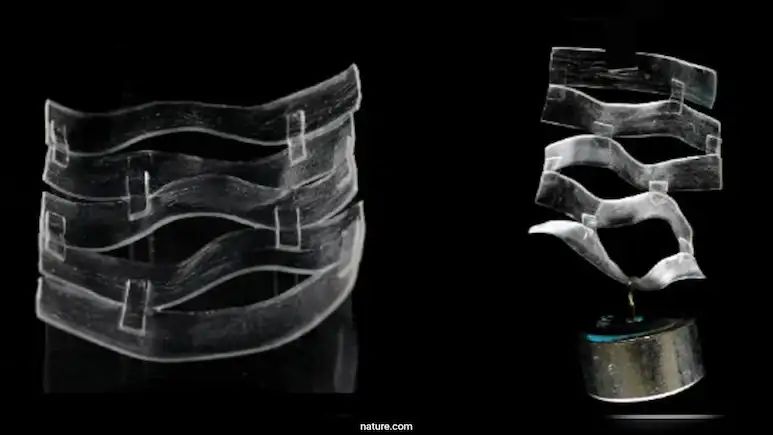

ವಿಜ್ಞಾನಿಗಳು ಚರ್ಮದಂತಹ ಹೈಡ್ರೋಜೆಲ್ ರಚಿಸಿದ್ದಾರೆ. ಇದು 24 ಗಂಟೆಗಳಲ್ಲಿ 90% ಗಾಯಗಳನ್ನು ಸಂಪೂರ್ಣವಾಗಿ ಗುಣಪಡಿಸುತ್ತದೆ.

ರೋಮಾಂಚಕಾರಿ ವೈಜ್ಞಾನಿಕ ಆವಿಷ್ಕಾರ ಇದಾಗಿದ್ದು, ಆಲ್ಟೊ ವಿಶ್ವವಿದ್ಯಾಲಯ ಮತ್ತು ಬೇರೂತ್ ವಿಶ್ವವಿದ್ಯಾಲಯದ ಸಂಶೋಧಕರು ಮಾನವ ಚರ್ಮದ ಗುಣಗಳನ್ನು ಅನುಕರಿಸುವ ಕ್ರಾಂತಿಕಾರಿ ಸ್ವಯಂ-ಗುಣಪಡಿಸುವ ಹೈಡ್ರೋಜೆಲ್ ಅನ್ನು ಅಭಿವೃದ್ಧಿಪಡಿಸಿದ್ದಾರೆ.

ಈ ನವೀನ ವಸ್ತುವು ಕೇವಲ ನಾಲ್ಕು ಗಂಟೆಗಳಲ್ಲಿ 90% ವರೆಗೆ ತನ್ನನ್ನು ತಾನೇ ಸರಿಪಡಿಸಿಕೊಳ್ಳಬಹುದು ಮತ್ತು 24 ಗಂಟೆಗಳಲ್ಲಿ ಸಂಪೂರ್ಣವಾಗಿ ಗಾಯ ವಾಸಿ ಮಾಡಬಹುದು. ಇದು ಗಾಯದ ಆರೈಕೆ, ಪುನರುತ್ಪಾದಕ ಔಷಧ ಮತ್ತು ಕೃತಕ ಚರ್ಮದ ತಂತ್ರಜ್ಞಾನಗಳಿಗೆ ಹೊಸ ಸಾಮರ್ಥ್ಯವನ್ನು ನೀಡುತ್ತದೆ ಎನ್ನಲಾಗಿದೆ.

ಜೆಲ್ಗಳು ಸಾಮಾನ್ಯವಾಗಿ ಕೂದಲಿನ ಚಿಕಿತ್ಸೆ ಸೇರಿ ದೈನಂದಿನ ಉತ್ಪನ್ನಗಳಲ್ಲಿ ಕಂಡುಬರುತ್ತವೆ. ಆದರೆ ಮಾನವ ಚರ್ಮದ ಸಂಕೀರ್ಣ ಗುಣಗಳನ್ನು ಪುನರಾವರ್ತಿಸುವುದು ಯಾವಾಗಲೂ ಒಂದು ಸವಾಲಾಗಿದೆ. ಚರ್ಮವು ಹೊಂದಿಕೊಳ್ಳುವ, ಬಾಳಿಕೆ ಬರುವ ಮತ್ತು ಗುಣಪಡಿಸುವ ಅಸಾಧಾರಣ ಸಾಮರ್ಥ್ಯವನ್ನು ಹೊಂದಿದೆ. ಇಲ್ಲಿಯವರೆಗೆ, ವಿಜ್ಞಾನಿಗಳು ಮಾನವ ಚರ್ಮದಲ್ಲಿ ಕಂಡುಬರುವ ನಮ್ಯತೆ ಮತ್ತು ಗುಣಪಡಿಸುವ ಗುಣಗಳನ್ನು ಸಂಯೋಜಿಸುವ ವಸ್ತುವನ್ನು ಅಭಿವೃದ್ಧಿಪಡಿಸಲು ಹೆಣಗಾಡಿದ್ದರು. ನ್ಯಾನೊಶೀಟ್-ವರ್ಧಿತ ಪಾಲಿಮರ್ ಎಂಟ್ಯಾಂಗಲ್ಮೆಂಟ್ ಮೂಲಕ ಸಾಧ್ಯವಾದ ಈ ಹೊಸ ಹೈಡ್ರೋಜೆಲ್ ಈ ಸಮಸ್ಯೆಯನ್ನು ಪರಿಹರಿಸಿದೆ.

ಈ ಮಹೋನ್ನತ ಆವಿಷ್ಕಾರವು ಮಾರ್ಚ್ 7ರಂದು ಪ್ರತಿಷ್ಠಿತ ಜರ್ನಲ್ ನೇಚರ್ ಮೆಟೀರಿಯಲ್ಸ್ ನಲ್ಲಿ ಪ್ರಕಟವಾದ ಅಧ್ಯಯನದಲ್ಲಿ ಕಂಡುಬಂದಿದೆ. ಸಂಶೋಧಕರು ಅತಿ ತೆಳುವಾದ, ದೊಡ್ಡ ನ್ಯಾನೊಶೀಟ್ಗಳನ್ನು ಸೇರಿಸುವ ಮೂಲಕ ಹೈಡ್ರೋಜೆಲ್ ಅನ್ನು ವರ್ಧಿಸಿದ್ದಾರೆ. ಹೈಡ್ರೋಜೆಲ್ಗಳು ಸಾಮಾನ್ಯವಾಗಿ ಮೃದು ಮತ್ತು ಮೆತ್ತಗಿರುತ್ತವೆ, ಆದರೆ ಈ ಹೊಸ ವಸ್ತುವು ನ್ಯಾನೊಶೀಟ್ಗಳ ನಡುವೆ ದಟ್ಟವಾಗಿ ಸಿಕ್ಕಿಹಾಕಿಕೊಂಡ ಪಾಲಿಮರ್ಗಳೊಂದಿಗೆ ಹೆಚ್ಚು ಸಂಘಟಿತ ರಚನೆಯನ್ನು ರೂಪಿಸುತ್ತದೆ. ಇದು ಹೈಡ್ರೋಜೆಲ್ ಅನ್ನು ಬಲಪಡಿಸುವುದಲ್ಲದೆ, ಹಾನಿಯ ನಂತರ ಅದು ಸ್ವತಃ ಗುಣವಾಗಲು ಅನುವು ಮಾಡಿಕೊಡುತ್ತದೆ ಎನ್ನಲಾಗಿದೆ.

ಸ್ವಯಂ-ದುರಸ್ತಿ ಮಾಡುವ ಜೆಲ್ ಗಾಯ ಗುಣಪಡಿಸುವುದು, ಔಷಧ ವಿತರಣೆ, ಮೃದು ರೊಬೊಟಿಕ್ಸ್ ಮತ್ತು ಪ್ರಾಸ್ಥೆಟಿಕ್ಸ್ ಸೇರಿದಂತೆ ವಿವಿಧ ಕ್ಷೇತ್ರಗಳಲ್ಲಿ ಒಂದು ರೋಮಾಂಚಕಾರಿ ಹೆಜ್ಜೆಯನ್ನು ನೀಡುತ್ತದೆ. ತ್ವರಿತವಾಗಿ ಮತ್ತು ಪರಿಣಾಮಕಾರಿಯಾಗಿ ಗುಣಪಡಿಸುವ ವಸ್ತುವಿನ ಸಾಮರ್ಥ್ಯವು ವೈದ್ಯಕೀಯ ಚಿಕಿತ್ಸೆಗಳನ್ನು ಮುಂದುವರೆಸಲು ಇದನ್ನು ಭರವಸೆಯನ್ನಾಗಿ ಮಾಡುತ್ತದೆ, ಸುಟ್ಟಗಾಯಗಳಿಗೆ ಒಳಗಾದವರು, ಶಸ್ತ್ರಚಿಕಿತ್ಸಾ ರೋಗಿಗಳು ಮತ್ತು ದೀರ್ಘಕಾಲದ ಗಾಯಗಳನ್ನು ಹೊಂದಿರುವವರಿಗೆ ವೇಗವಾಗಿ ಚೇತರಿಸಿಕೊಳ್ಳುವ ಭರವಸೆ ನೀಡುತ್ತದೆ ಎಂದು ಹೇಳಲಾಗಿದೆ.